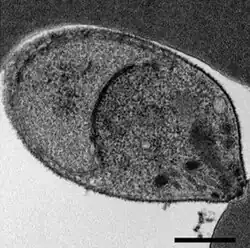

A Plasmodium knowlesi merozoite attaching to a red blood cell

P. knowlesi largely resembles other Plasmodium species in its cell biology. Its genome consists of 23.5 megabases of DNA separated into 14 chromosomes.[5] It contains approximately 5200 protein-coding genes, 80% of which have orthologs present in P. falciparum and P. vivax.[5] The genome contains two large gene families that are unique to P. knowlesi: the SICAvar (schizont-infected cell agglutination variant) family, which is involved in displaying different antigens on the parasite surface to evade the immune system, and the Kir (knowlesi interspersed repeat) family, involved in adhering parasitized red blood cells to blood vessel walls.[5]

As an apicomplexan, P. knowlesi has several distinctive structures at its apical end that are specialized for invading host cells. These include the large bulbous rhoptries, smaller micronemes, and dispersed dense granules, each of which secretes effectors to enter and modify the host cell.[6][7] Like other apicomplexans, P. knowlesi also has two organelles of endosymbiotic origin: a single large mitochondrion and the apicoplast, both of which are involved in the parasite's metabolism.[8]